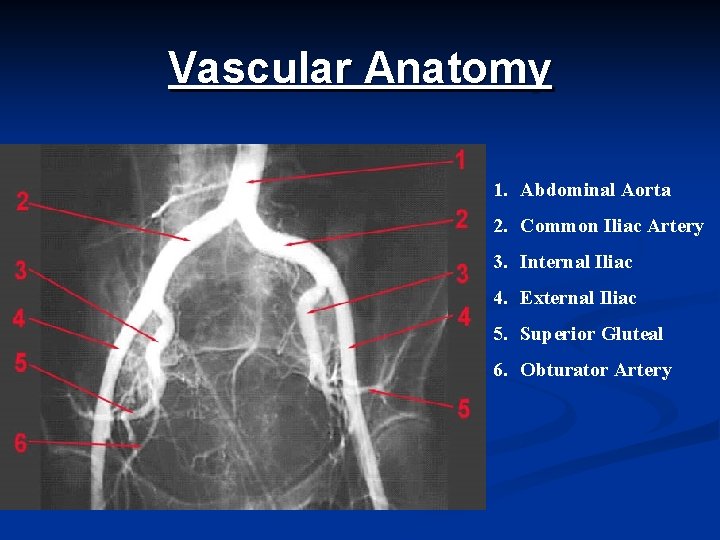

Vascular Anatomy 1. Abdominal Aorta 2. Common Iliac Artery 3. Internal Iliac 4. External Iliac 5. Superior Gluteal 6. Obturator Artery